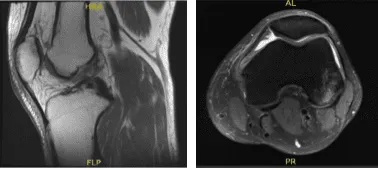

MRI – 3T Left Knee Non Contrast

MRI result was presented today and shown complex tear of the posterior horn of the medial meniscus, small horizontal cleavage tear of the body of the lateral meniscus, impaction injury of the posterior non weight bearing aspect of the lateral femoral condyle with small fracture,

Grade 2 medial collateral ligament injury with vertical longitudinal tear, Contusion in the inferior medial aspect of the patella, Moderate joint effusion with synovitis.